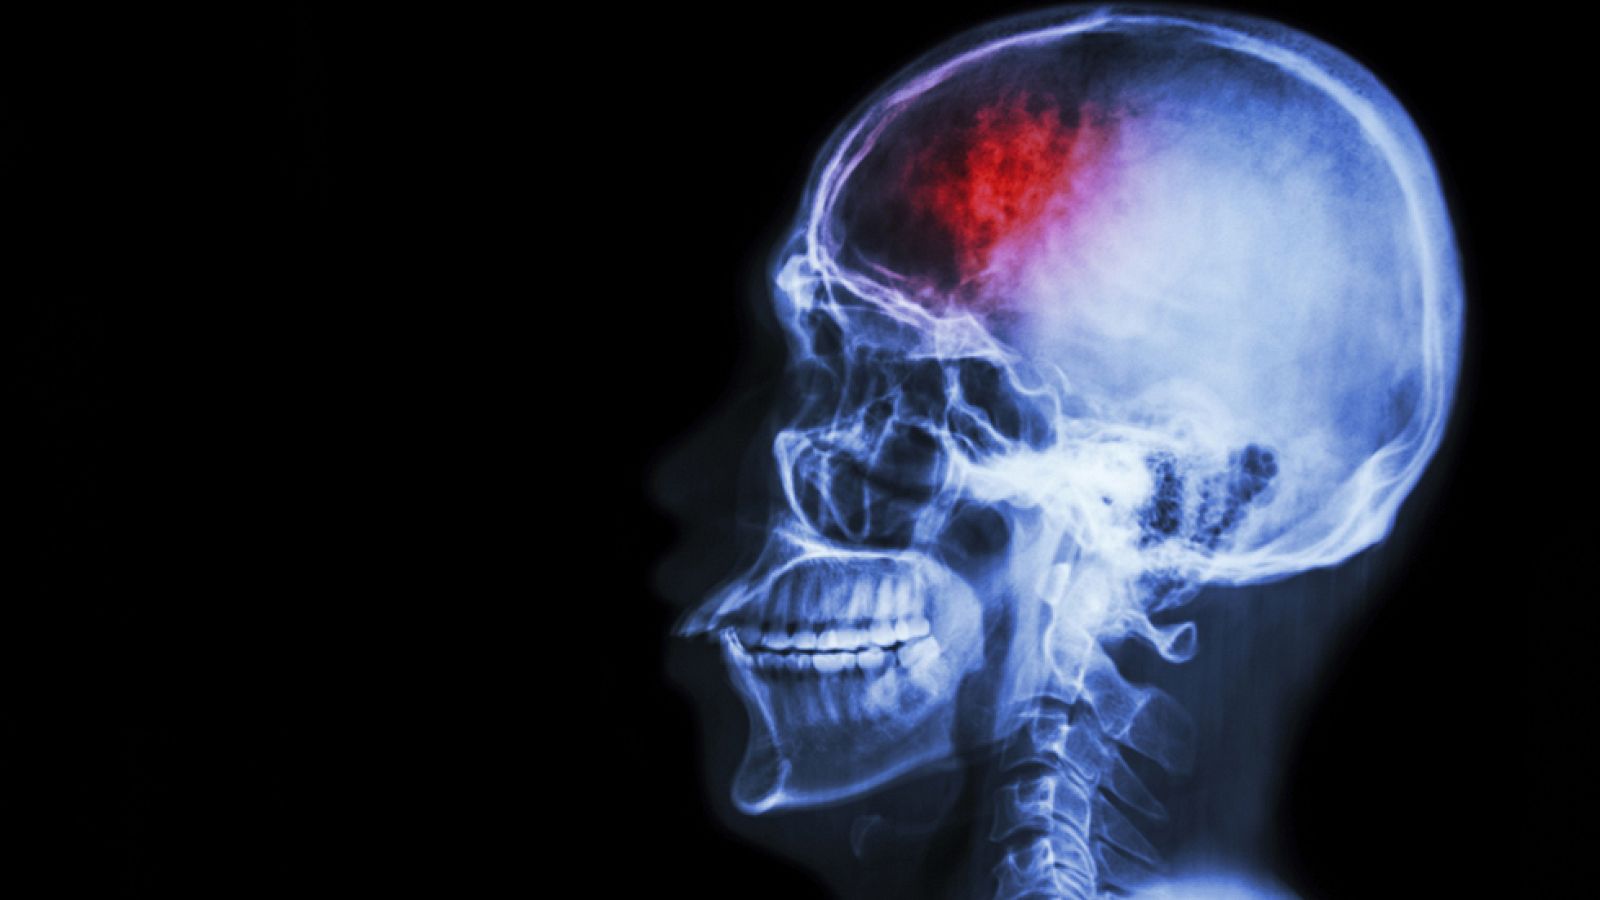

Nos fijamos en las arterias del cerebro y en una situación muy peligrosa: cuando se obstruyen. El doctor Carlos Tejero, Vocal de la Sociedad Española de Neurología, nos habla de la falta de riego cerebral, qué síntomas da, qué se nota, cómo prevenirlo a tiempo y qué pastillas mejoran la circulación.